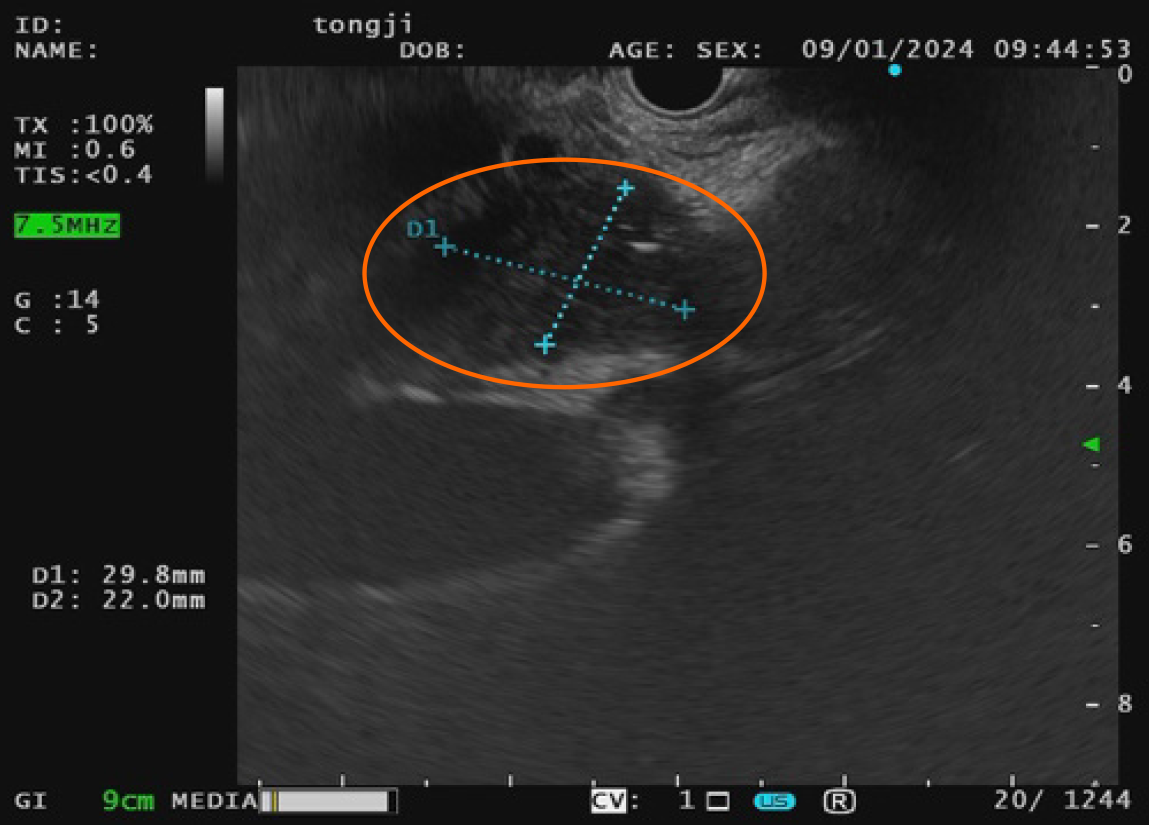

Figure 3 Endoscopic ultrasound-fine needle aspiration images.

Endoscopic ultrasound reveals a hypoechoic mass in the pancreatic head measuring approximately 29.8 mm × 22.0 mm (orange circle). Fine needle aspiration was performed for cytological and histopathological evaluation.